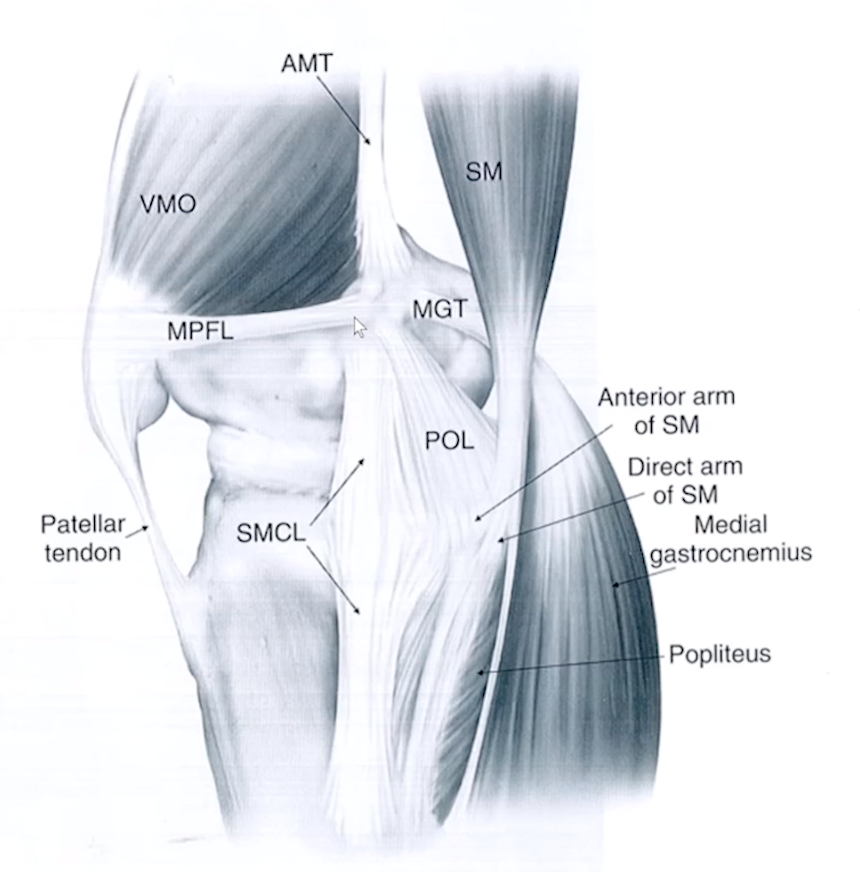

Medial Patellofemoral ligament (MPFL)

• Thicker deeper dark line

• The more superficial, thin and whispier line is the medial retinaculum

Posteriormedial corner of knee

• 5 parts

• Posterior oblique ligament = major player

• Oblique popliteal ligament

• Meniscotibial ligament

• Semimembranosus tendon

• Medial meniscus